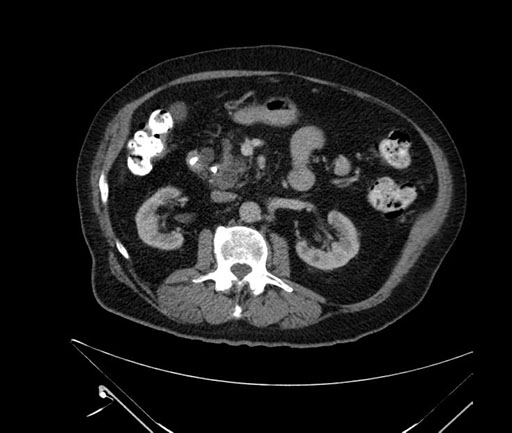

Whipple (pancreaticoduodenectomy) [case 7]

Imaging Analysis

Look through the patient's CT scan to identify any areas of concern for the necessary procedure.

Based on your CT findings, which issue(s) would give reason for "planned slowing down moment(s)" in this case?

Considering a standard Whipple procedure, what step(s) of the operation would you do differently in this case?